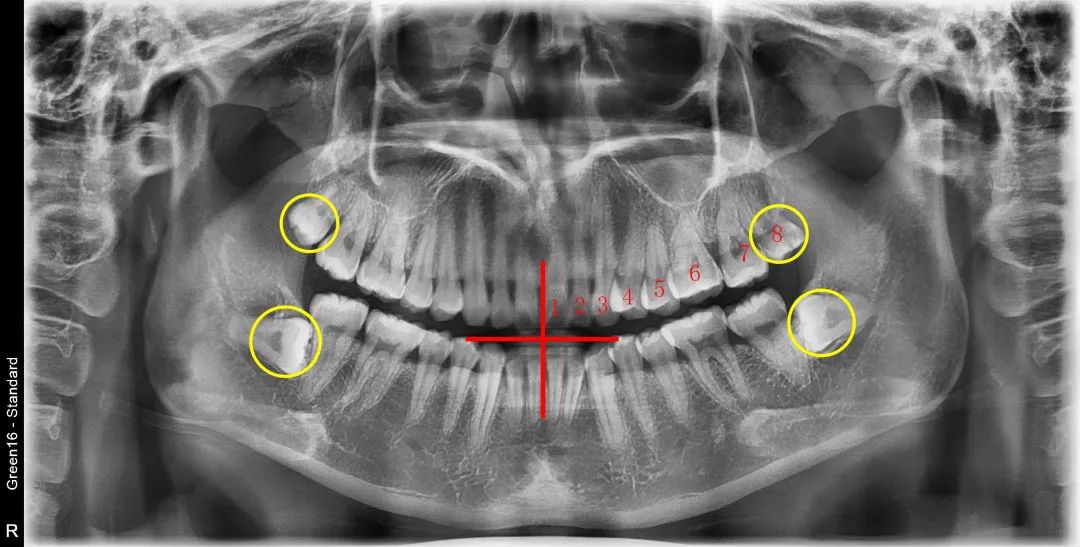

來,對(duì)著鏡子,張大嘴巴。

把手放在兩顆門牙中間的牙縫,然后開始往后數(shù),如果數(shù)到了第8顆牙齒......

▲配圖僅供科普,不作為醫(yī)療癥狀診療依據(jù)

那么恭喜這位朋友——你是被智齒之神寵愛的幸運(yùn)鵝!

但沒數(shù)到也并不代表沒有!也許它只是“藏”得比較深,在粘膜或骨內(nèi),讓你尋不到蹤跡。

所以,小貝建議,還是到牙科醫(yī)院拍個(gè)片子看看更確切。